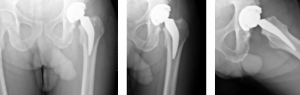

Case Report #2

John Aldridge, MD

Hampton Roads Orthopedics and Sports Medicine

A 62-year-old African American male weighing 185lbs diagnosed with osteo/degenerative arthritis received Advita’s Alte on Neck Preserving stem with a Biolox® delta femoral head and InteGrip® acetabular shell. The patient underwent general anesthesia using a direct anterior surgical approach with an incision size of 9cm. There was an estimated blood loss of 200cc and surgery duration was 30minutes. The patient was discharged the same day as the operation with a walker to in home care for rehabilitation.

Pre-Op AP Pelvis

Harris Hip Score 48 (max=100) | Oxford Hip Score 19 (max=48)

6-Week Post-Op

Harris Hip Score 96 (max=100) | Oxford Hip Score 38 (max=48)

3-Month Post-Op

Harris Hip Score 89 (max=100) | Oxford Hip Score 44 (max=48)

1-Year Post-Op

Harris Hip Score 96 (max=100) | Oxford Hip Score 46 (max=48)

CONCLUSION

This patient presented with low Harris Hip and Oxford Hip scores before his total hip replacement. The direct anterior approach, which was used in this surgery, has been associated with faster functional recovery than the posterolateral approach. One year after surgery, his Harris Hip score increased by more than 50.0 percent, and his Oxford Hip score increased by more than 58.7 percent. The outcomes of his surgery continue to be followed each year, and the patient is satisfied with his total hip replacement. •